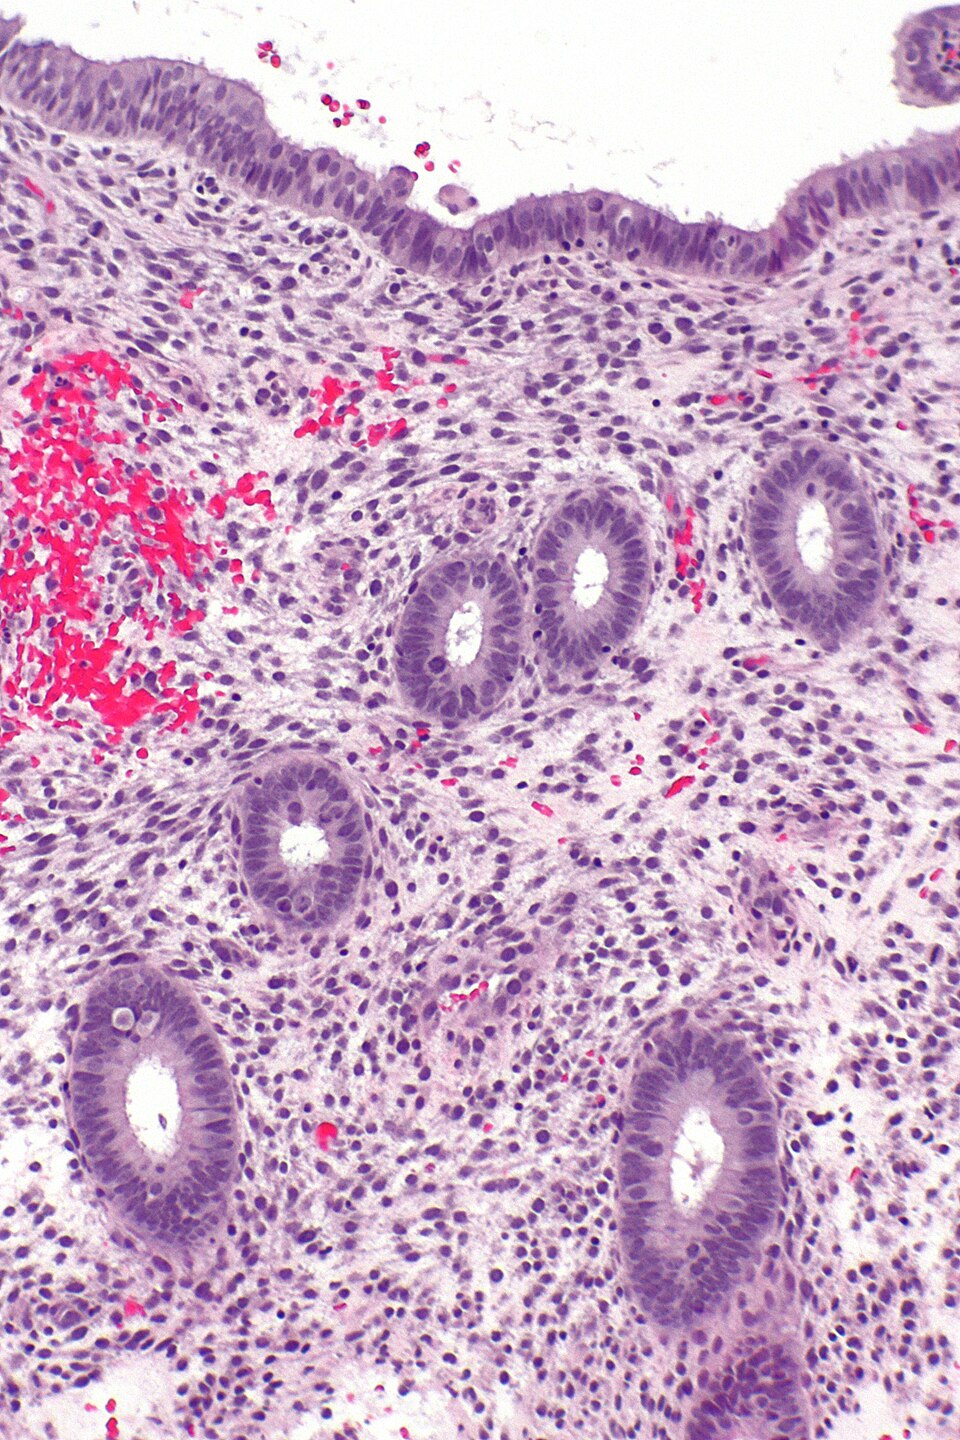

Adenomyosis

Endometriumdrüsen im Myometrium.